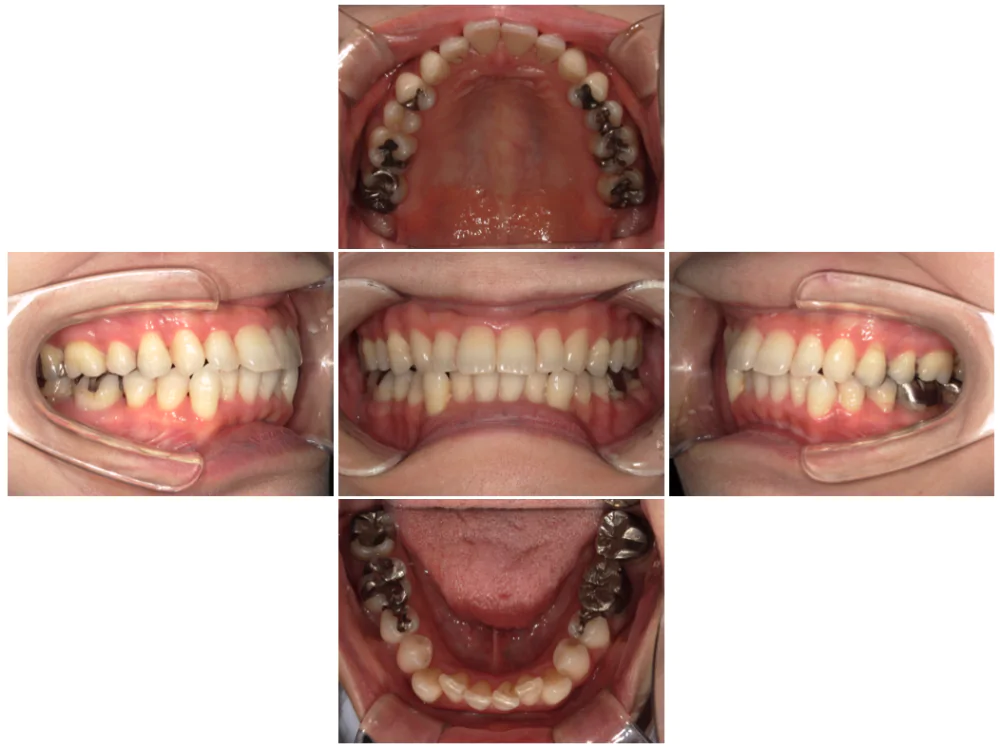

症例4

| 来院時の主訴 | 全体的なガタガタ |

| 医院での対応や適用装置 | マウスピース矯正装置を使用して主訴である |

| 通院期間 | 11ヶ月 |

| 通院回数 | 5回 |

| 治療費用総額 | 852,500円(税込) |

| リスクと副作用 | 矯正治療による歯の移動に伴う痛み、歯根吸収、虫歯 |